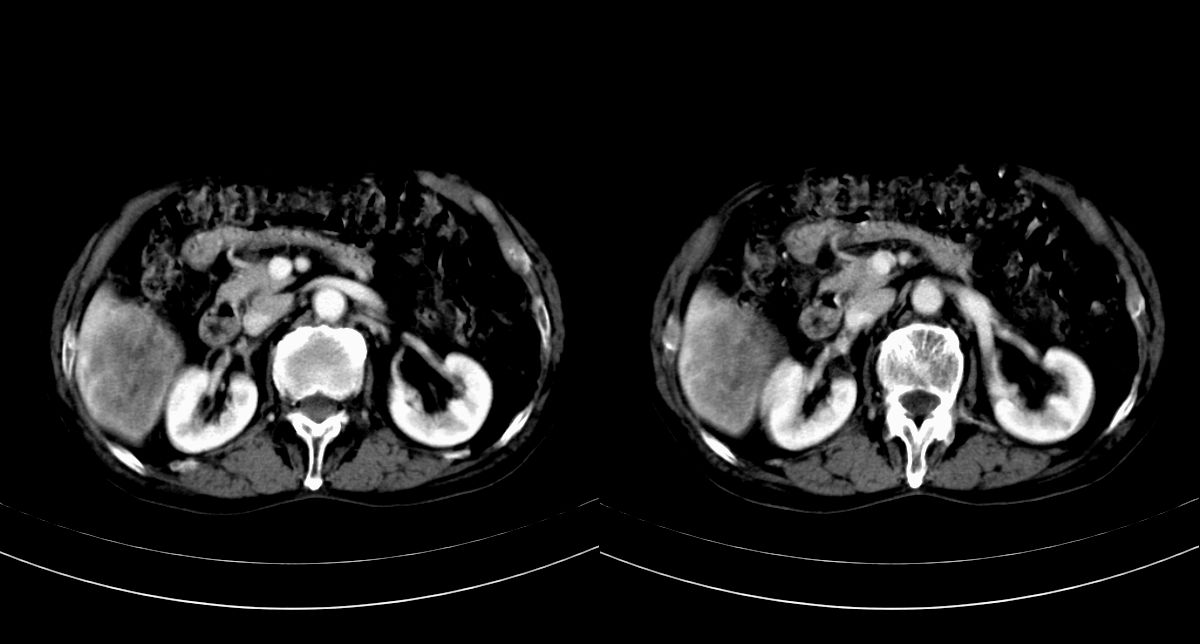

男,79y,无不适。体检发现肝脏占位。

肝内多发低密度结节,增强动脉期明显强化,门脉期逐渐下降,内有液化坏死区。

肝内多发低密度结节灶,增强动脉期明显不规则环状强化,;门脉期逐渐下降,肿瘤壁厚薄不一,内有坏死液化区。